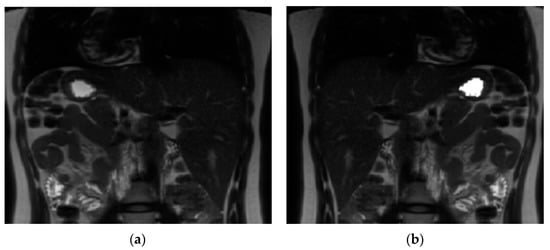

2.7. Image Analysis